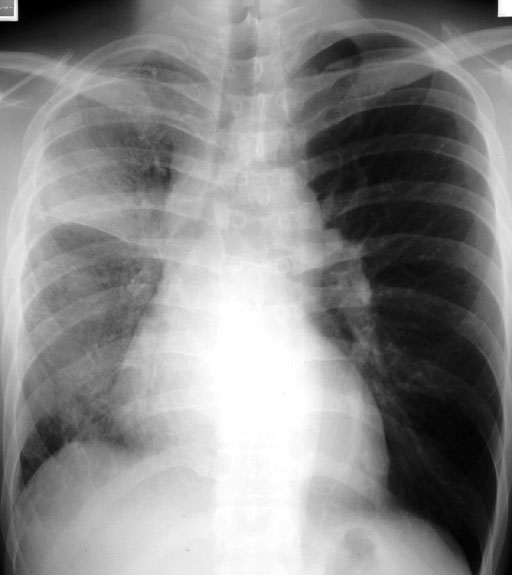

症例1:24歳,男性

喀血

4日前に喀血があり,緊急入院となる.喀血はその後落ち着き,軽度の呼吸苦があるが,胸痛はない.

7年前に右自然気胸を起こし,他院にてブラ縫縮と胸膜癒着術を施行されている

図1 胸部単純X線写真